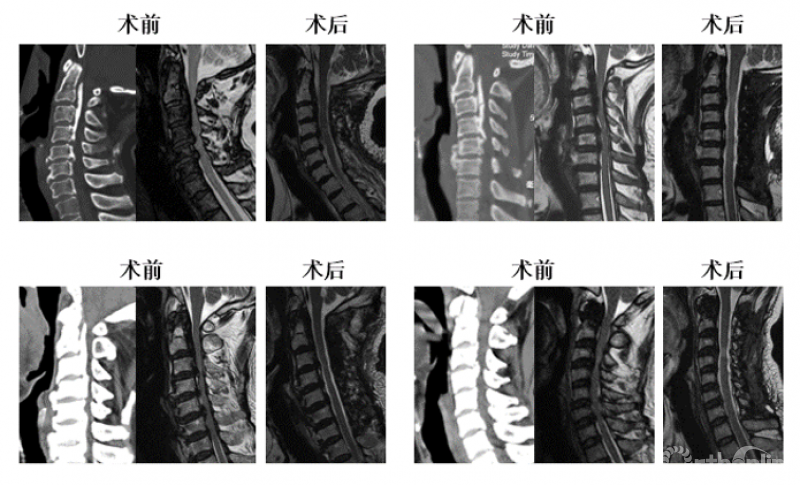

对于该例患者,C2/3间隙水平有轻度脊髓压迫,脊髓受压最重的节段仍然在C3/4水平。我们进行了再次手术,并向头侧扩大减压范围至C2,术后不仅C2/3水平的轻微压迫得到解除,C3/4水平脊髓压迫也明显去除了(图3),神经功能改善。

图3 术后核磁显示脊髓减压充分

最后,我们回到病例一,利用上述研究结果指导临床决策:C3/4水平致压物中矢径8.71mm>7.1mm,所以C3-7减压势必残留压迫,应选择C2-7减压,术后获得了9.34mm的ACS,充分解除了脊髓压迫(图7)。

图7

当OPLL累及上颈椎时,需要权衡是否需要切除C1后弓的情况并不少见,本研究有助于合理确定寰椎后弓切除的指征。除了寰椎水平脊髓腹侧(如颈椎后纵韧带骨化延伸至寰椎前弓)或背侧(寰椎后弓发育不良或畸形)存在压迫这一常见手术指征,在寰椎至枢椎体中部范围内,当致压物的矢状径超过采用C2-7减压能获得的SVCD(8.5mm)时,向头端扩大减压,行寰椎后弓切除是获得充分减压的有效手段(图4)。

图4